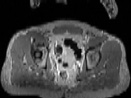

Visible Human male: Sectio transversalis 1856

CT

NMR

Pd                          / T2 \                         T1